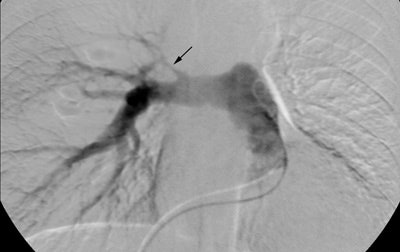

A pulmonary arteriogram revealed no left upper lobe perfusion. The right upper lobe pulmonary artery is narrowed (black arrow)

Selective left pulmonary arteriogram revealed the vessel to be patent, although irregular and narrowed. A delayed run was not performed, but the findings were felt to be consistent with pulmonary venous obstruction based upon the CT scan findings.